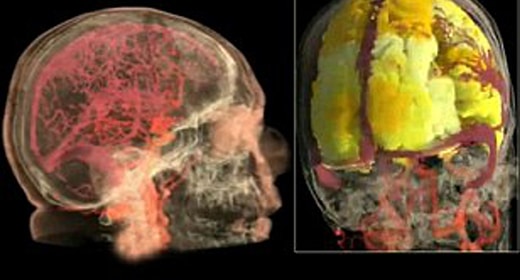

Nan Wise, estudiante de doctorado, terapeuta sexual y asociada del proyecto de investigación de 54 años, aceptó ser el conejillo de indias. La conectaron a un escáner de imágenes por resonancia magnética funcional (fMRI) y se estimularon mientras la máquina tomaba “instantáneas” de su cerebro.

cada dos segundos, en 80 regiones diferentes, el guardián informó. Luego, el profesor Barry Komisaruk y su equipo unieron estas instantáneas en una película animada. La película es la primera de su tipo.

Al ver el vídeo, es difícil no sentirse estimulado visualmente sólo por los colores. (En realidad, es solo cuestión de tiempo antes de que alguien en YouTube decida publicarlo con “Firework” de Katy Perry sonando de fondo). La escala de colores, que va del rojo oscuro al amarillo claro, representa la cantidad de oxígeno que se utiliza en esa sección del cerebro. Cuando el orgasmo alcanza su clímax, la imagen se ilumina.

Komisaruk presentó recientemente su investigación en la Sociedad de Neurociencia en Washington, DC, aunque no ha sido publicada en una revista revisada por pares. Espera que su trabajo no sólo permita a los científicos comprender por qué algunos hombres y mujeres tienen problemas para alcanzar el orgasmo, sino también comprender la reacción de nuestro cuerpo al placer en su conjunto.

Mantiene su cerebro sano: Tener un orgasmo no sólo ejercita tu corazón, sino también tu cabeza. Barry Komisaruk, Ph.D. dijo Cosmopolita que los orgasmos en realidad nutren el cerebro con oxígeno. «Las imágenes de resonancia magnética funcional muestran que el cerebro de las mujeres utiliza mucho más oxígeno de lo habitual durante el orgasmo», dice Komisaruk.